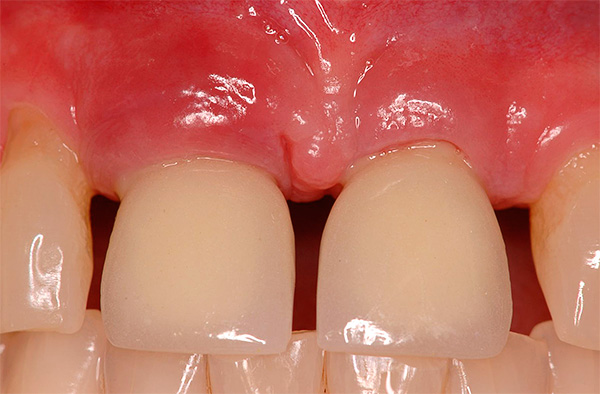

A foto abaixo mostra um exemplo correspondente (a inflamação começou 10 anos após a instalação do implante):

Abaixo, veremos o que pode ser feito para evitar esse resultado adverso.No entanto, antes disso, vamos falar sobre quais sensações são consideradas normais após o implante dentário e quais devem ser consideradas sintomas de peri-implantite, ameaçando evoluir para rejeição do implante.

A foto abaixo mostra um exemplo de inflamação do tecido na área de um implante instalado: